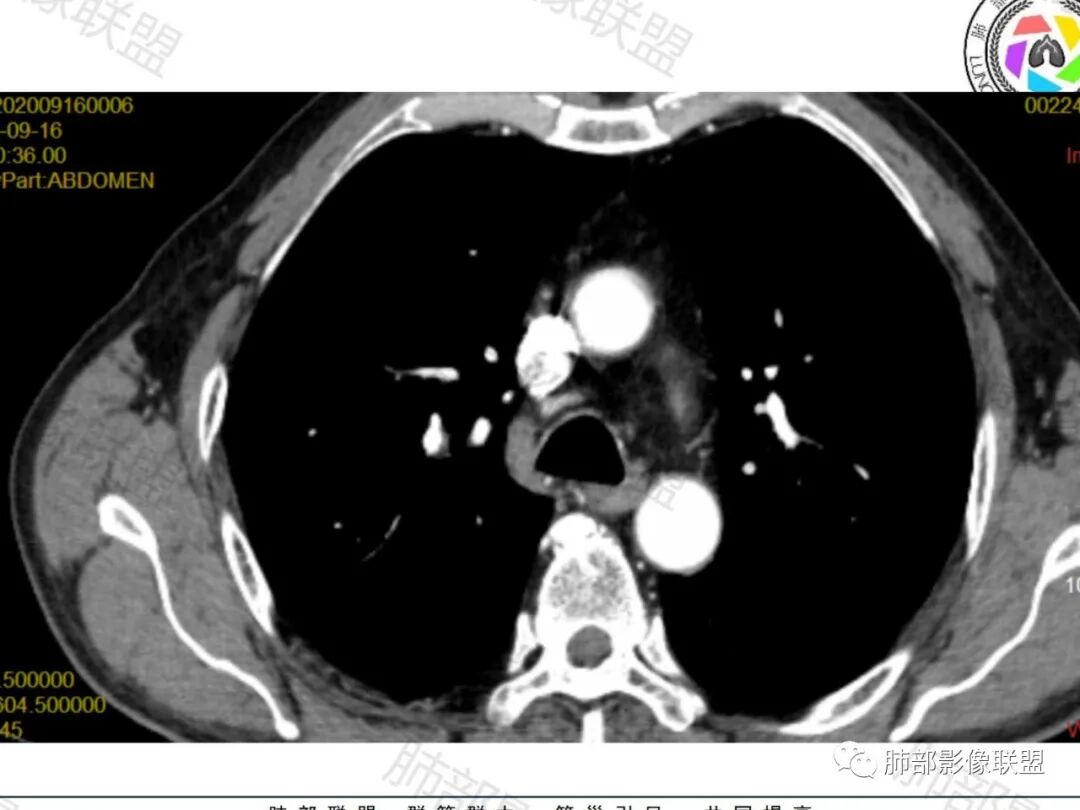

右肺下叶一类圆形肿块影,内缘边缘光滑,外缘边界模糊,可见磨玻璃影,整体以彭隆为主,部分边缘包绕支气管,平扫密度尚均匀,增强后不均匀强化,部分与膈肌黏连,临床,62岁男性,无症状,考虑恶性:腺癌,鳞癌,神经内分泌癌,肉瘤

老年人,偶然发现,右肺下叶类圆形软组织占位,密度较均匀,病灶边缘光滑,无毛刺分叶,支气管血管受挤压向外移位,增强病灶强化较均匀。考虑恶性肿瘤,外向内生长,肉瘤,肉瘤样癌,癌肉瘤,其次神经内分泌癌。

老年男性,右肺下叶软组织肿物,整体外形光整,周围组织推挤,可见血管贴边,貌似又有血管进入,整体强化均匀,考虑良性可能大,硬化性肺细胞瘤?鉴别sft

老年男性,偶然发现,说明平时没有症状,边缘光整,血管贴边,整体强化均匀,倾向于良性或者低度恶性(PSP?类癌?)

老年男性,肿瘤标志物高,右肺占位,边界清楚,内部密度均匀,坏死不明显,无明显分叶,血管贴边,考虑PSP,老年男性,肿块大,需鉴别恶性,肉瘤样癌?高分化鳞癌?

男性,62,胆结石入院胸部CT偶然发现占位。肿标稍增高,右肺下叶胸膜下肿块,边缘尚清,密度较均匀,增强明显强化,血管贴边,空气新月征?静脉期可见低强化区,首先考虑PSP,鉴别肉瘤样癌及神经内分泌肿瘤

老年男性,右肺下叶肿块,边缘光整,血管贴边,部分血管进入,整体强化尚均匀,考虑大细胞癌,鉴别PSP、SFT

右肺下叶类圆形软组织肿块,病灶边缘光滑,无明显毛刺分叶,支气管受压推移,血管贴边,部分血管进入病灶,增强病灶强化不均匀,内可见低密度,病灶与右侧膈肌分界不清,考虑神经内分泌肿瘤,大细胞癌。鉴别PSP

老年男性,肿瘤标志物高,右肺下叶类圆形肿块,宽基底与胸膜相连,边缘光整,密度均匀,周围气管及血管受压推移,延迟强化,其内见纤细血管,似有小低密度灶,首先考虑间叶组织恶性肿瘤,良性平滑肌瘤、纤维瘤不除外

患者中老年男性,检查发现右下肺占位。查肺癌标记物稍有升高。血常规白细胞计数稍降低。胸部CT:右肺下叶后基底段类圆形肿块,边缘光滑,边界清楚,周边见气管受压扩张,增强轻度强化,内见点状低密度影,见血管贴边。综合考虑良性过低度恶性病变,PSP可能,其它恶性肿瘤待排。

支气管,血管均受压推移,类圆形占位,无分叶,无毛刺,光滑表面,明显均匀强化,倾向于psp,鉴别错构瘤,肉瘤,肉瘤样癌,类癌等神经内分泌肿瘤,转移,imt。

老年男性,检查发现右下肺占位。CT:右肺下叶一类圆形肿块影,膨隆,无分叶,边缘基本光滑,近端支气管推挤狭窄,与胸膜夹角为锐角,增强见不均匀强化,未见坏死,近端见血管贴边,胸壁脂肪间隙清楚。考虑良性病变——PSP可能性大。鉴别神经内分泌癌、肉瘤、SFT。

右肺下叶软组织肿块,边缘光滑,临近血管受压变形且增粗,增强后见斑片状低强化区,界不清,实性部分见条状血管影,边缘光滑,考虑PSP可能,肿块与支气管关系不密切,腺癌,腺鳞癌不符合,肿块内增强后血管走形自然,间叶组织起源肉瘤不符

右肺下叶肿块,呈外带大内带小的椭圆形改变(内带受支气管及血管挤压原因),边缘光滑,无分叶毛刺,支气管受压,增强后,均匀延迟强化,动脉期见血管贴边,静脉期内部瘤样血管强化区,相邻胸膜无侵犯,纵隔无淋巴结肿大,符合PSP,不鉴别。

男,62岁,体检发现病变。

胸部CT:右肺下叶一类圆形肿块影,边界清楚,大部分边缘光滑、外缘边界模糊,邻近支气管推移、血管贴边,病灶内可见分枝状血管,平扫密度尚均匀,增强后大部分均匀延迟强化,部分与膈肌黏连、尾征?考虑:类Ca>PSP>SFT。鉴别肉瘤样Ca,CD等。

肿块位于周围(起自细支气管呼吸道上皮),均匀膨胀生长(符合良性的生长特点),病灶内部大部分密度较均匀,部分小低密度不强化区(囊变),增强强化较明显,边缘血管增粗贴边,临近支气管受压,支持PSP。